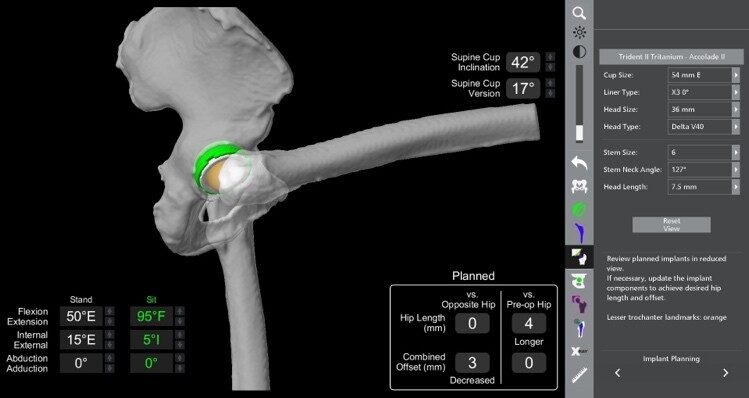

Dr. Duff is highly experienced in advanced joint reconstruction techniques, including:

These procedures are tailored to your anatomy, activity level, and long-term goals. Many patients report a dramatic improvement in mobility, independence, and quality of life after surgery.